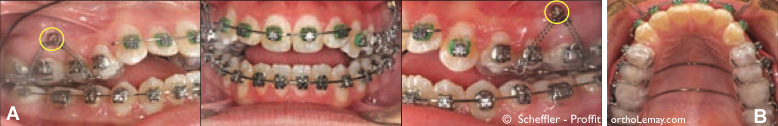

Fig (4) – Après 10 mois de traitement, les dents sont alignées (correction des rotations et du chevauchement dentaire) et les mini-vis d’ancrage furent posées. (A) Appareils orthodontiques en bouche avec les mini-vis d’ancrage indiquées par les cercles jaunes. Des ressorts de traction sont attachées entre les vis et des crochets sur l’appareil d’ancrage collé aux dents (visible en (B)). L’appareil d’ancrage et les mini-vis d’ancrage peuvent être utilisées sans la pose de brackets. Lors de la pose de l’appareil d’ancrage, la béance antérieure semblera augmenter à cause de l’épaisseur de plastique (acrylique) entre les dents mais ceci se corrigera à mesure que l’ingression des dents postérieures se produira et la béance antérieure fermera.